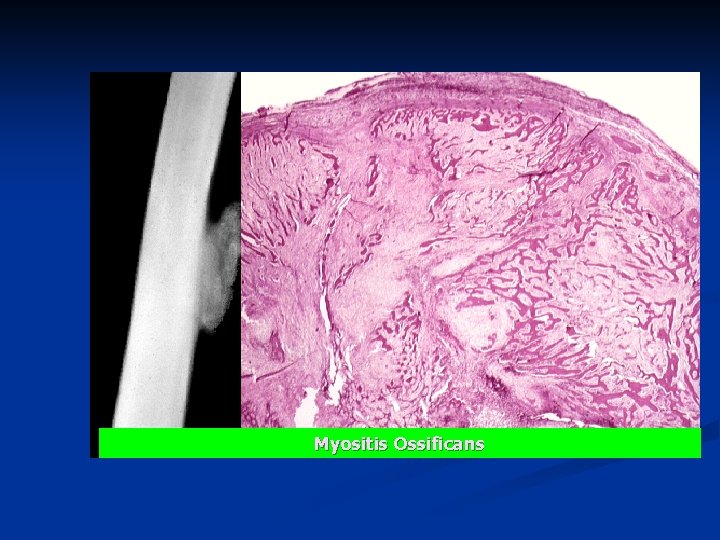

Myositis Ossificans A nonneoplastic tumor-like lesion n Trauma to skeletal muscle hemorrhage distrophic calcification heterotropic ossification n It must be distinguished from extraosseous osteogenic sarcoma. n Clinical x-rays: n n peripherally calcifying (ossifying) lesion located in the soft tissues or next to bone.

n Microscopically, newly formed bone n matures toward the periphery of the lesion, n whereas the center or interior of the lesion is cellular and poorly differentiated. n n The presence of peripheral maturity and central immaturity of the lesion is called "zoning phenomenon" and is characteristic of myositis ossificans but lacking in osteogenic sarcoma.

Myositis Ossificans